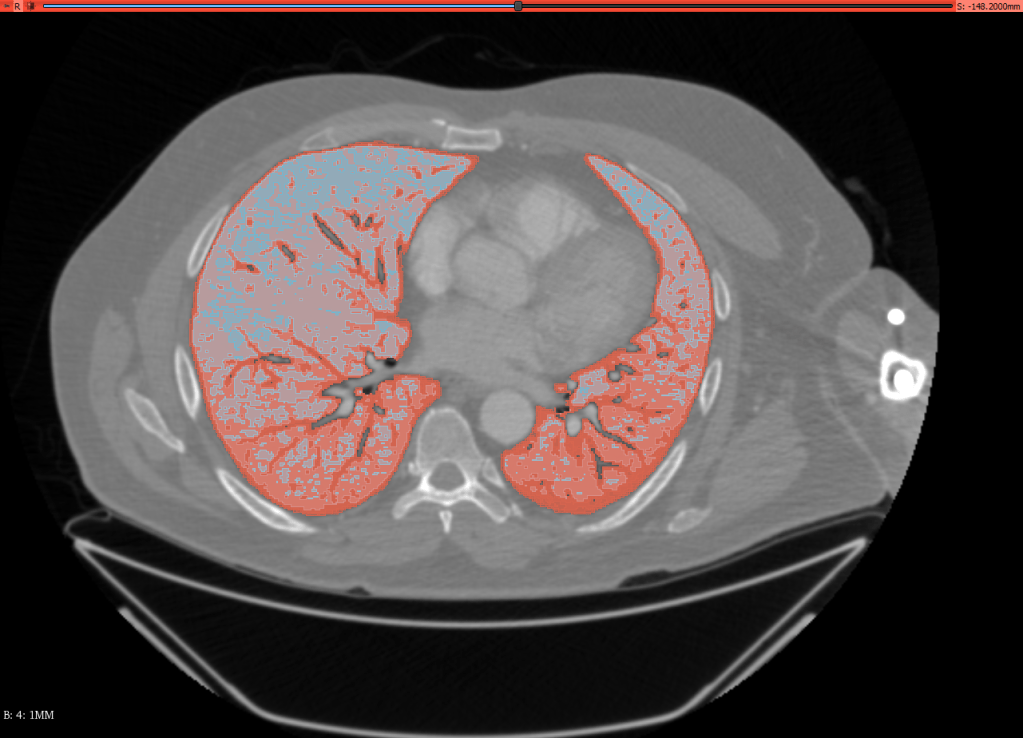

Reconstrucción 3D de Pulmones afectados por Covid-19

Utilizando bases de datos abiertas a la investigación y programas de código abierto 3D Slicer, fue posible realizar segmentaciones de alta precisión para cuantificar los daños a pulmones afectados por Covid-19

Esta es una sección de un TAC que ha sido segmentado según la densidad del tejido pulmonar, se puede apreciar como la parte posterior de los pulmones se empieza a compactar y a deteriorar.